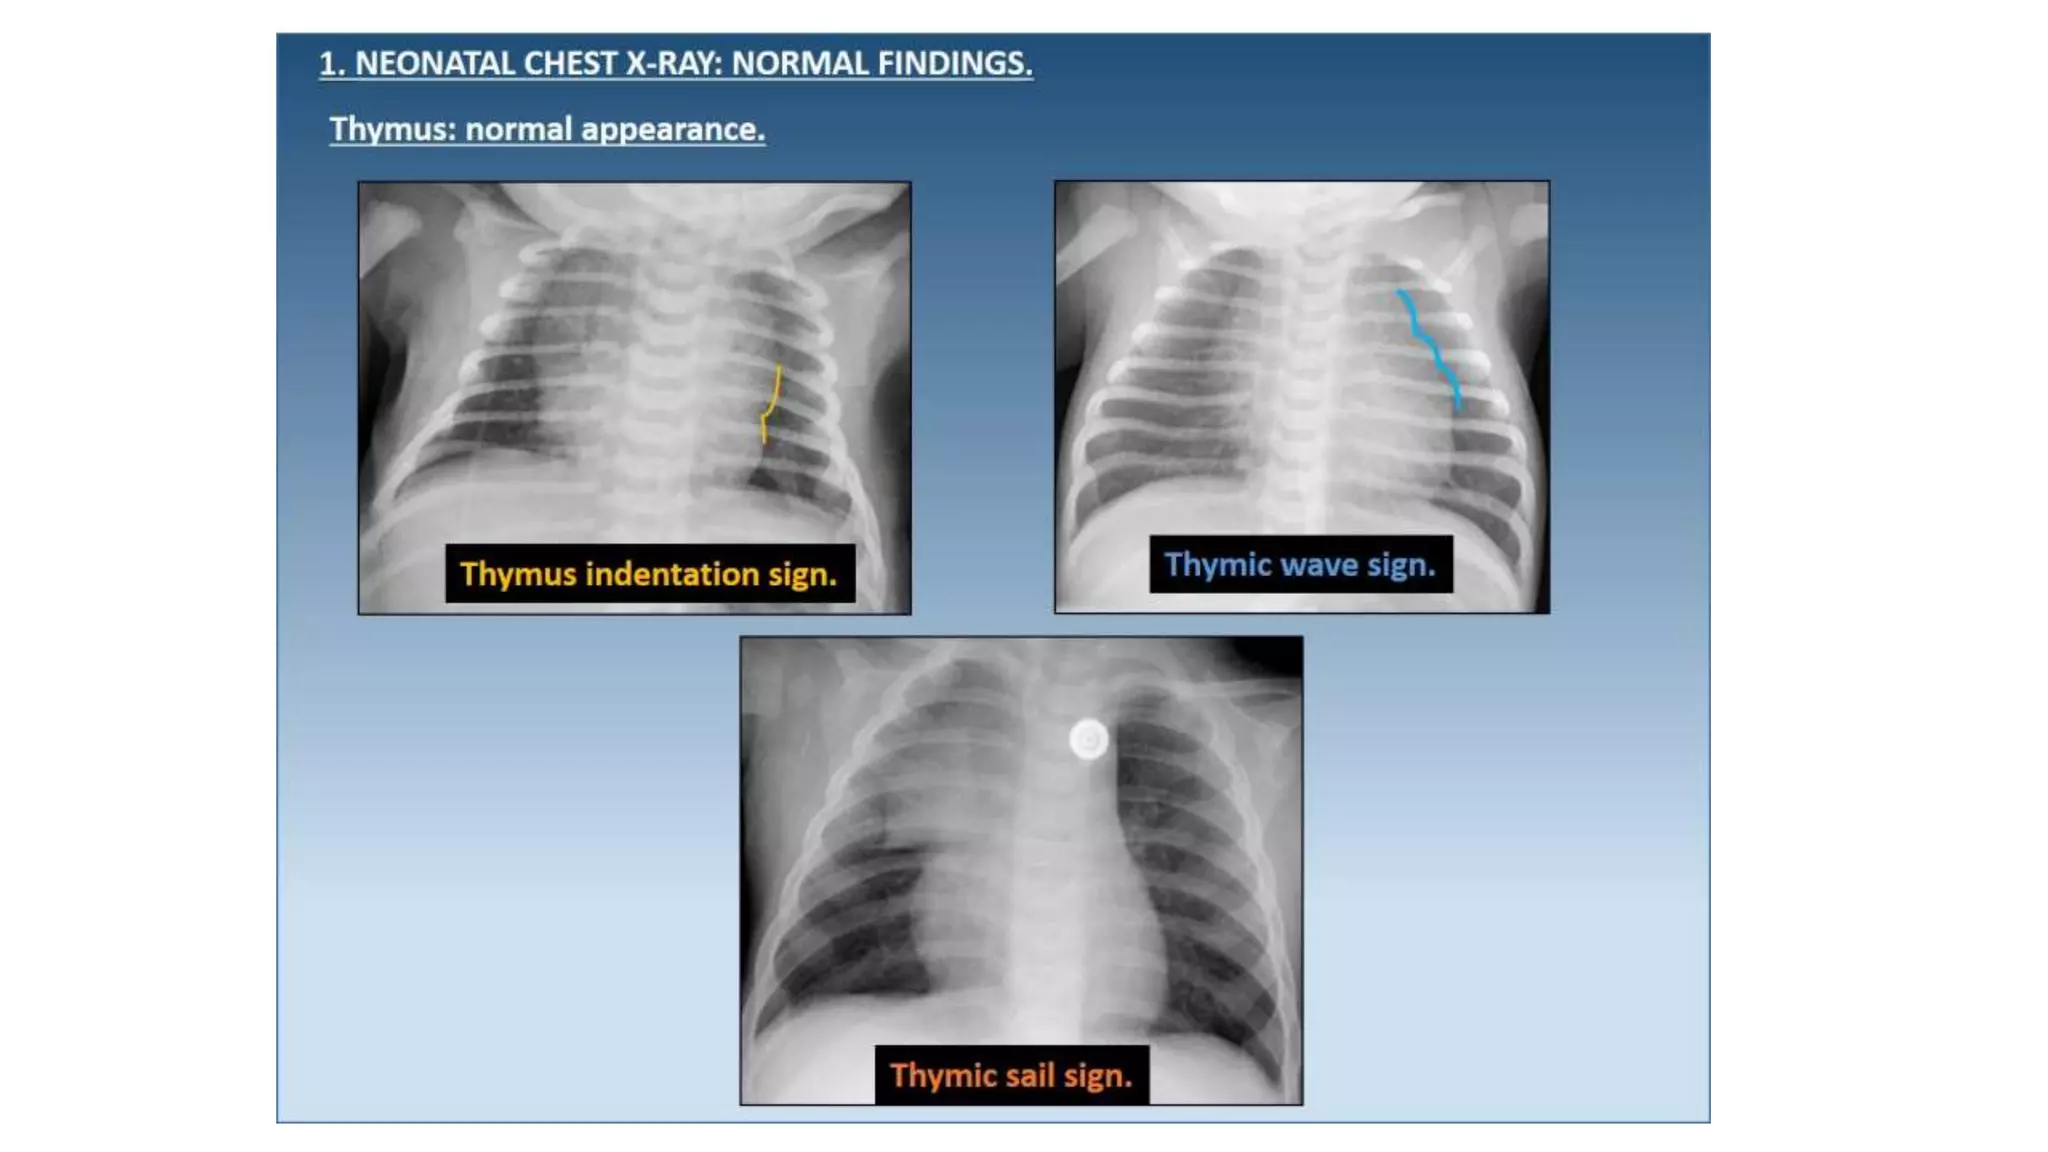

This document provides an overview of neonatal chest x-rays, including when they should and should not be performed, what a normal x-ray looks like, common positions of tubes and catheters, and common causes of respiratory distress in neonates. It discusses the appearance of a normal chest x-ray as well as conditions like respiratory distress syndrome, transient tachypnea of the newborn, meconium aspiration syndrome, and pneumonia. Surgical conditions like diaphragmatic hernia and esophageal atresia are also reviewed.